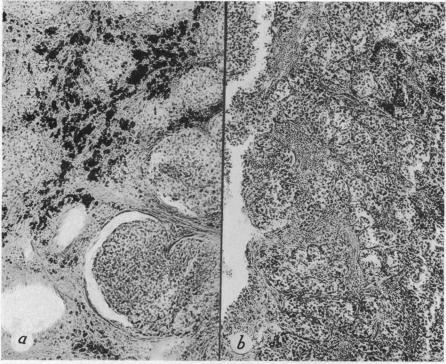

TUMORS OF THE CAROTID BODY: CLINICAL AND PATHOLOGIC CONSIDERATIONS OF TWENTY TUMORS AFFECTING NINETEEN PATIENTS (ONE BILATERAL).

Ann Surg. 1941 Nov;114(5):820-33. doi: 10.1097/00000658-194111000-00003.